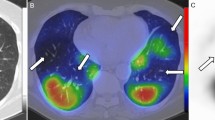

All the patients survived through the study period and were discharged from the hospital. We repeated the DECT imaging in two patients within 1 month. Previous PDs were improved in the first patient (Fig. 5). PDs in the second patient who had a pulmonary thromboembolism were improved with stable findings related to the emboli.

A 47-year-old male with coronavirus disease 2019 (COVID-19). The dual-energy computed tomography (DECT) angiography perfusion map (a) demonstrates multiple perfusion deficits, especially in the right lung (arrowheads). These areas do not match with the multiple ground-glass opacities seen on conventional CT (b). Follow-up DECT angiography 25 days after the first exam. Perfusion map (c) and conventional CT images (d) demonstrate a more prominent regression in the perfusion deficits compared with the conventional CT findings